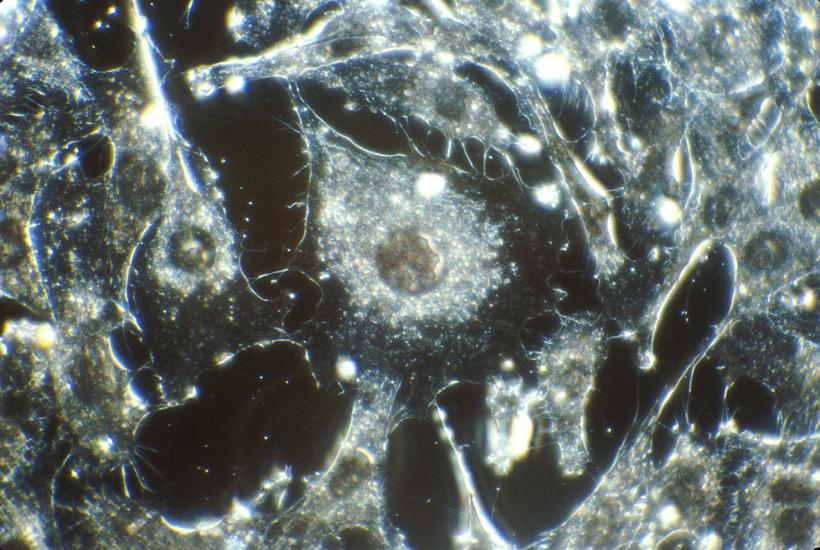

Молекулярно-генетические исследования, включая секвенирование ДНК и РНК, стали повседневным инструментом в работе врачей. Особенно активно они применяются в онкологии и педиатрии. Как рассказала Наталья Бодунова, заведующая Центром персонализированной медицины МКНЦ им. Логинова, "в некоторых специальностях такие исследования уже стали рутиной".

Иван Абрамов, врач-биолог Центра персонализированной медицины, рассказал о важности применения широких генетических панелей — они позволяют врачам подбирать точечное лечение и быстрее ставить диагноз. Это — шаг к персонализированным протоколам терапии.